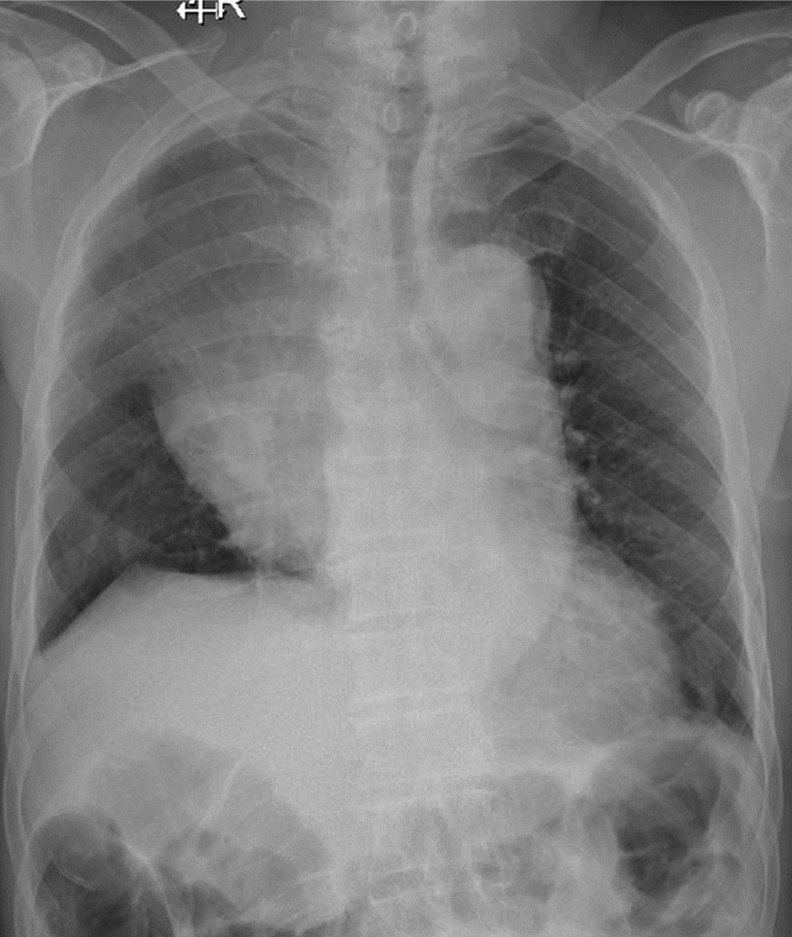

1-Thâm nhiểm phế nang lan tỏa phổi (T) => Viêm phổi 2-Hình ảnh nhiều u trung thất (T) => Lymphoma 3-Tràn dịch màng phổi (P) 4-Tràn dịch màng phổi (T)